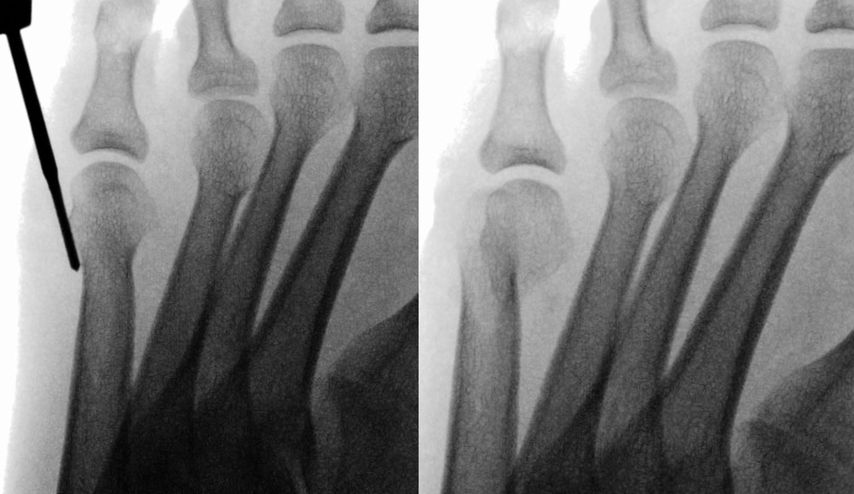

Aufgrund von Problemen mit der Helal- und der Weil-Osteotomie wurden minimalinvasive Techniken entwickelt. Schon 1991 beschrieb Whitedie minimalinvasive distale Metatarsalosteotomie („Distal Metaphyseal Metatarsal Osteotomy“, DMMO).13 Die Endposition des Metatarsalköpfchens wird durch den Zug der intakten Weichteile und die postoperative Vollbelastung diktiert. Vor allem de Prado, Redfern und Vernois haben diese Technik propagiert. Hier wird unter Zuhilfenahme einer minimalinvasiven Fräse mit hohem Drehmoment eine extraartikuläre Osteotomie des Metatarsales von proximal plantar nach distal dorsal durchgeführt. Das plantare Fragment wird unter Druck von distal nach proximal verschoben. Postoperative Zügelverbände gemeinsam mit dem intakten Weichteilmantel sollen die Osteotomie in der gewünschten Stellung stabilisieren (Abb. 4).

Johansen et al.14 präsentierten eine randomisierte Studie mit jeweils 30 Patienten. Die Komplikationsrate war bis auf das vermehrte Auftreten von hypertrophen Narben (0 vs. 9%) in der offenen Weil-Gruppe gleich. Die postoperative Bewegungseinschränkung, die „floating toe“ und eine Plantarflexions- bzw. Hyperextensionsfehlstellung traten bei der offenen Weil-Osteotomie häufiger auf. Die Operationszeit war bei der DMMO-Gruppe signifikant kürzer, dafür war die Röntgenbestrahlungszeit signifikant länger.